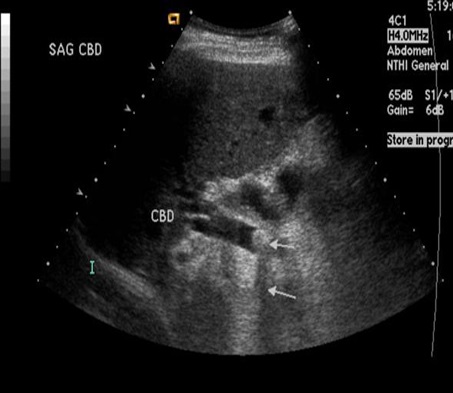

Aspect hyperechoriche

avec de zone de faible acoustique posterieure d'une calcul du

canal hepatique ( fleche blanche ) . Voie

biliaire en amont est tres dilate . Image

echographique per cutanee en coupe a longitudinal de

voie biliare principale |